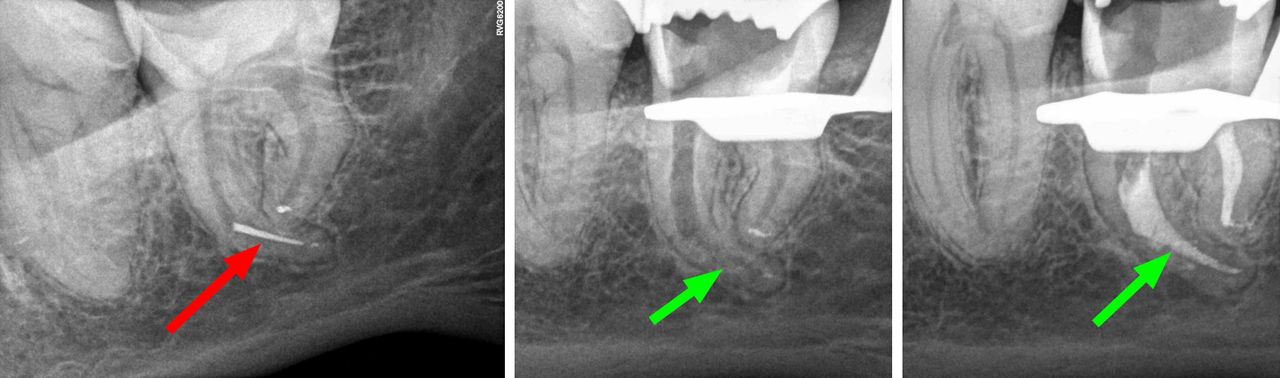

- Usuwanie złamanych narzędzi kanałowych oraz innych ciał obcych pozostawionych w kanałach korzeniowych

- Specjalizujemy się w powtórnym leczeniu kanałowym i leczeniu powikłań co oznacza, że mamy wieloletnie doświadczenie w usuwaniu złamanych instrumentów kanałowych w szybki, bezbolesny i nieinwazyjny sposób. Dr Gończowski jest autorem specjalistycznego zestawu mikroinstrumentów (FRS®) przeznaczonych do usuwania ciał obcych z kanałów korzeniowych